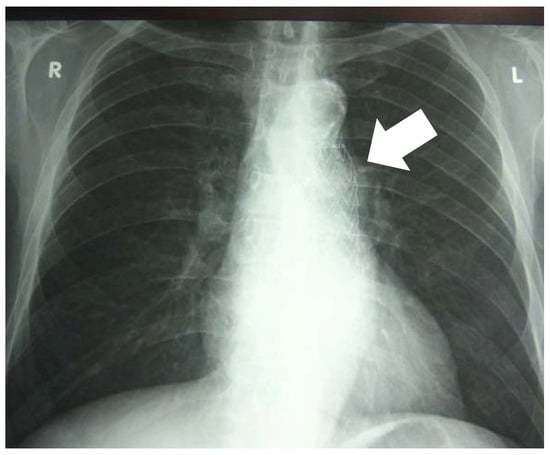

Tuberculous Aneurysm of the Thoracic Aorta: A Diagnostic and Therapeutic Challenge in the Modern Era

Introduction: Tuberculous aneurysm of the thoracic aorta (TBAA) is an extremely rare but potentially fatal manifestation of tuberculosis (TB). Clinical presentation may include hemoptysis in the absence of parenchymal lung abnormalities. Case report: We presented a 62-year-old male with cough, chest pain, [...] Read more.

Introduction: Tuberculous aneurysm of the thoracic aorta (TBAA) is an extremely rare but potentially fatal manifestation of tuberculosis (TB). Clinical presentation may include hemoptysis in the absence of parenchymal lung abnormalities. Case report: We presented a 62-year-old male with cough, chest pain, and minimal hemoptysis. Diagnostic evaluation confirmed an aneurysm of the descending thoracic aorta at a site previously treated with endovascular repair, with no imaging findings suggestive of pulmonary TB. Bronchoscopy revealed blood in the main bronchi without an identifiable endobronchial source. The diagnosis of TB was established by polymerase chain reaction (PCR) testing of bronchial aspirate obtained during bronchoscopy. Emergency surgical intervention was recommended because of an impending aortic rupture, but the patient declined surgery. Standard antituberculous therapy was initiated, and the patient subsequently developed drug-induced liver injury, prompting temporary cessation of treatment. The clinical course was later complicated by the development of an aortoesophageal fistula (AEF), with significant implications for prognosis. Conclusions: Early recognition of TBAA, along with a multidisciplinary approach that integrates advanced diagnostic modalities, timely vascular intervention, and carefully managed antituberculous therapy, is essential to reduce mortality and optimize treatment outcomes. Full article

Show Figures

Figure 1